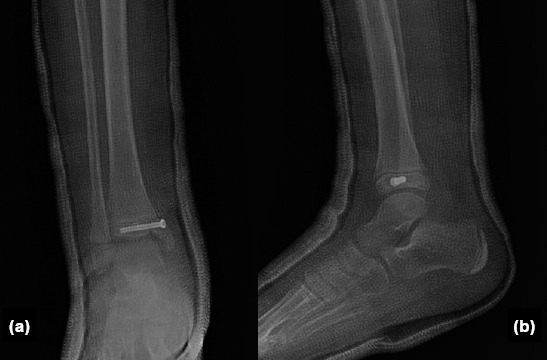

Methods: This retrospective study analyzed outcomes of 13 patients, aged 6-17 years, who underwent surgical treatment for McFarland fractures between 2021 and 2023 at a Level 1 Trauma Center. Surgical methods included screw fixation, K-wire fixation, and tension wire fixation. Outcome measures included radiological deformity assessments (lateral distal tibial angle [LDTA], anterior distal tibial angle [ADTA]), range of motion (ROM), Foot and Ankle Ability Measure (FAAM) scores for functional assessment, and Visual Analogue Scale (VAS) scores for pain. Comparisons were made between the operated and non-operated limbs.

Results: LDTA and ADTA values showed minimal differences between the operated and non-operated limbs, indicating successful surgical realignment (p<0.05). Although slight ROM limitations were observed in the operated limb, high FAAM scores and low VAS scores reflected good functional recovery and effective pain management. Correlation analysis revealed a moderate positive correlation (r=0.45) between FAAM scores and ROM, and a weaker correlation (r=0.32) between FAAM scores and radiological alignment.

Conclusion: Surgical treatment of McFarland fractures resulted in favorable clinical and radiological outcomes, with minimal limitations in ROM and significant improvements in alignment and functional recovery. However, ongoing follow-up is essential, particularly in younger patients, to monitor and manage the risk of potential growth disturbances.